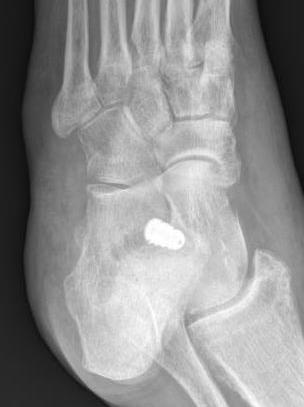

Subtalar arthroeresis

implantimplantimplant

Concept

Sinus tarsi implants limit excessive pronation

Endosinotarsal - implant in the sinus tarsi

Exosinotarsal - screw external to the sinus tarsi